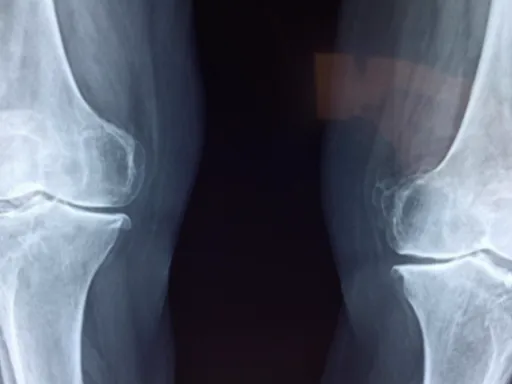

나이가 들면서 무릎 관절의 연골이 닳아 없어지는 퇴행성 관절염은 무릎 앞쪽뿐만 아니라 뒤쪽에도 통증을 유발할 수 있어요. 특히 관절염이 진행되어 관절 간격이 좁아지면, 무릎을 구부리거나 펼 때 뼈끼리 부딪히는 듯한 둔탁한 통증이 무릎 뒤쪽으로 느껴질 수 있답니다. 또한, 관절염으로 인해 무릎 주변 근육이 약해지거나 불균형해지면서 무릎 뒤쪽에 과도한 부담이 가해져 통증이 심화되기도 하죠. 무릎이 붓고 열감이 느껴지면서 움직임이 둔해지는 증상과 함께 무릎 뒤쪽의 뻐근함이 동반된다면, 퇴행성 관절염의 가능성을 염두에 두어야 해요.